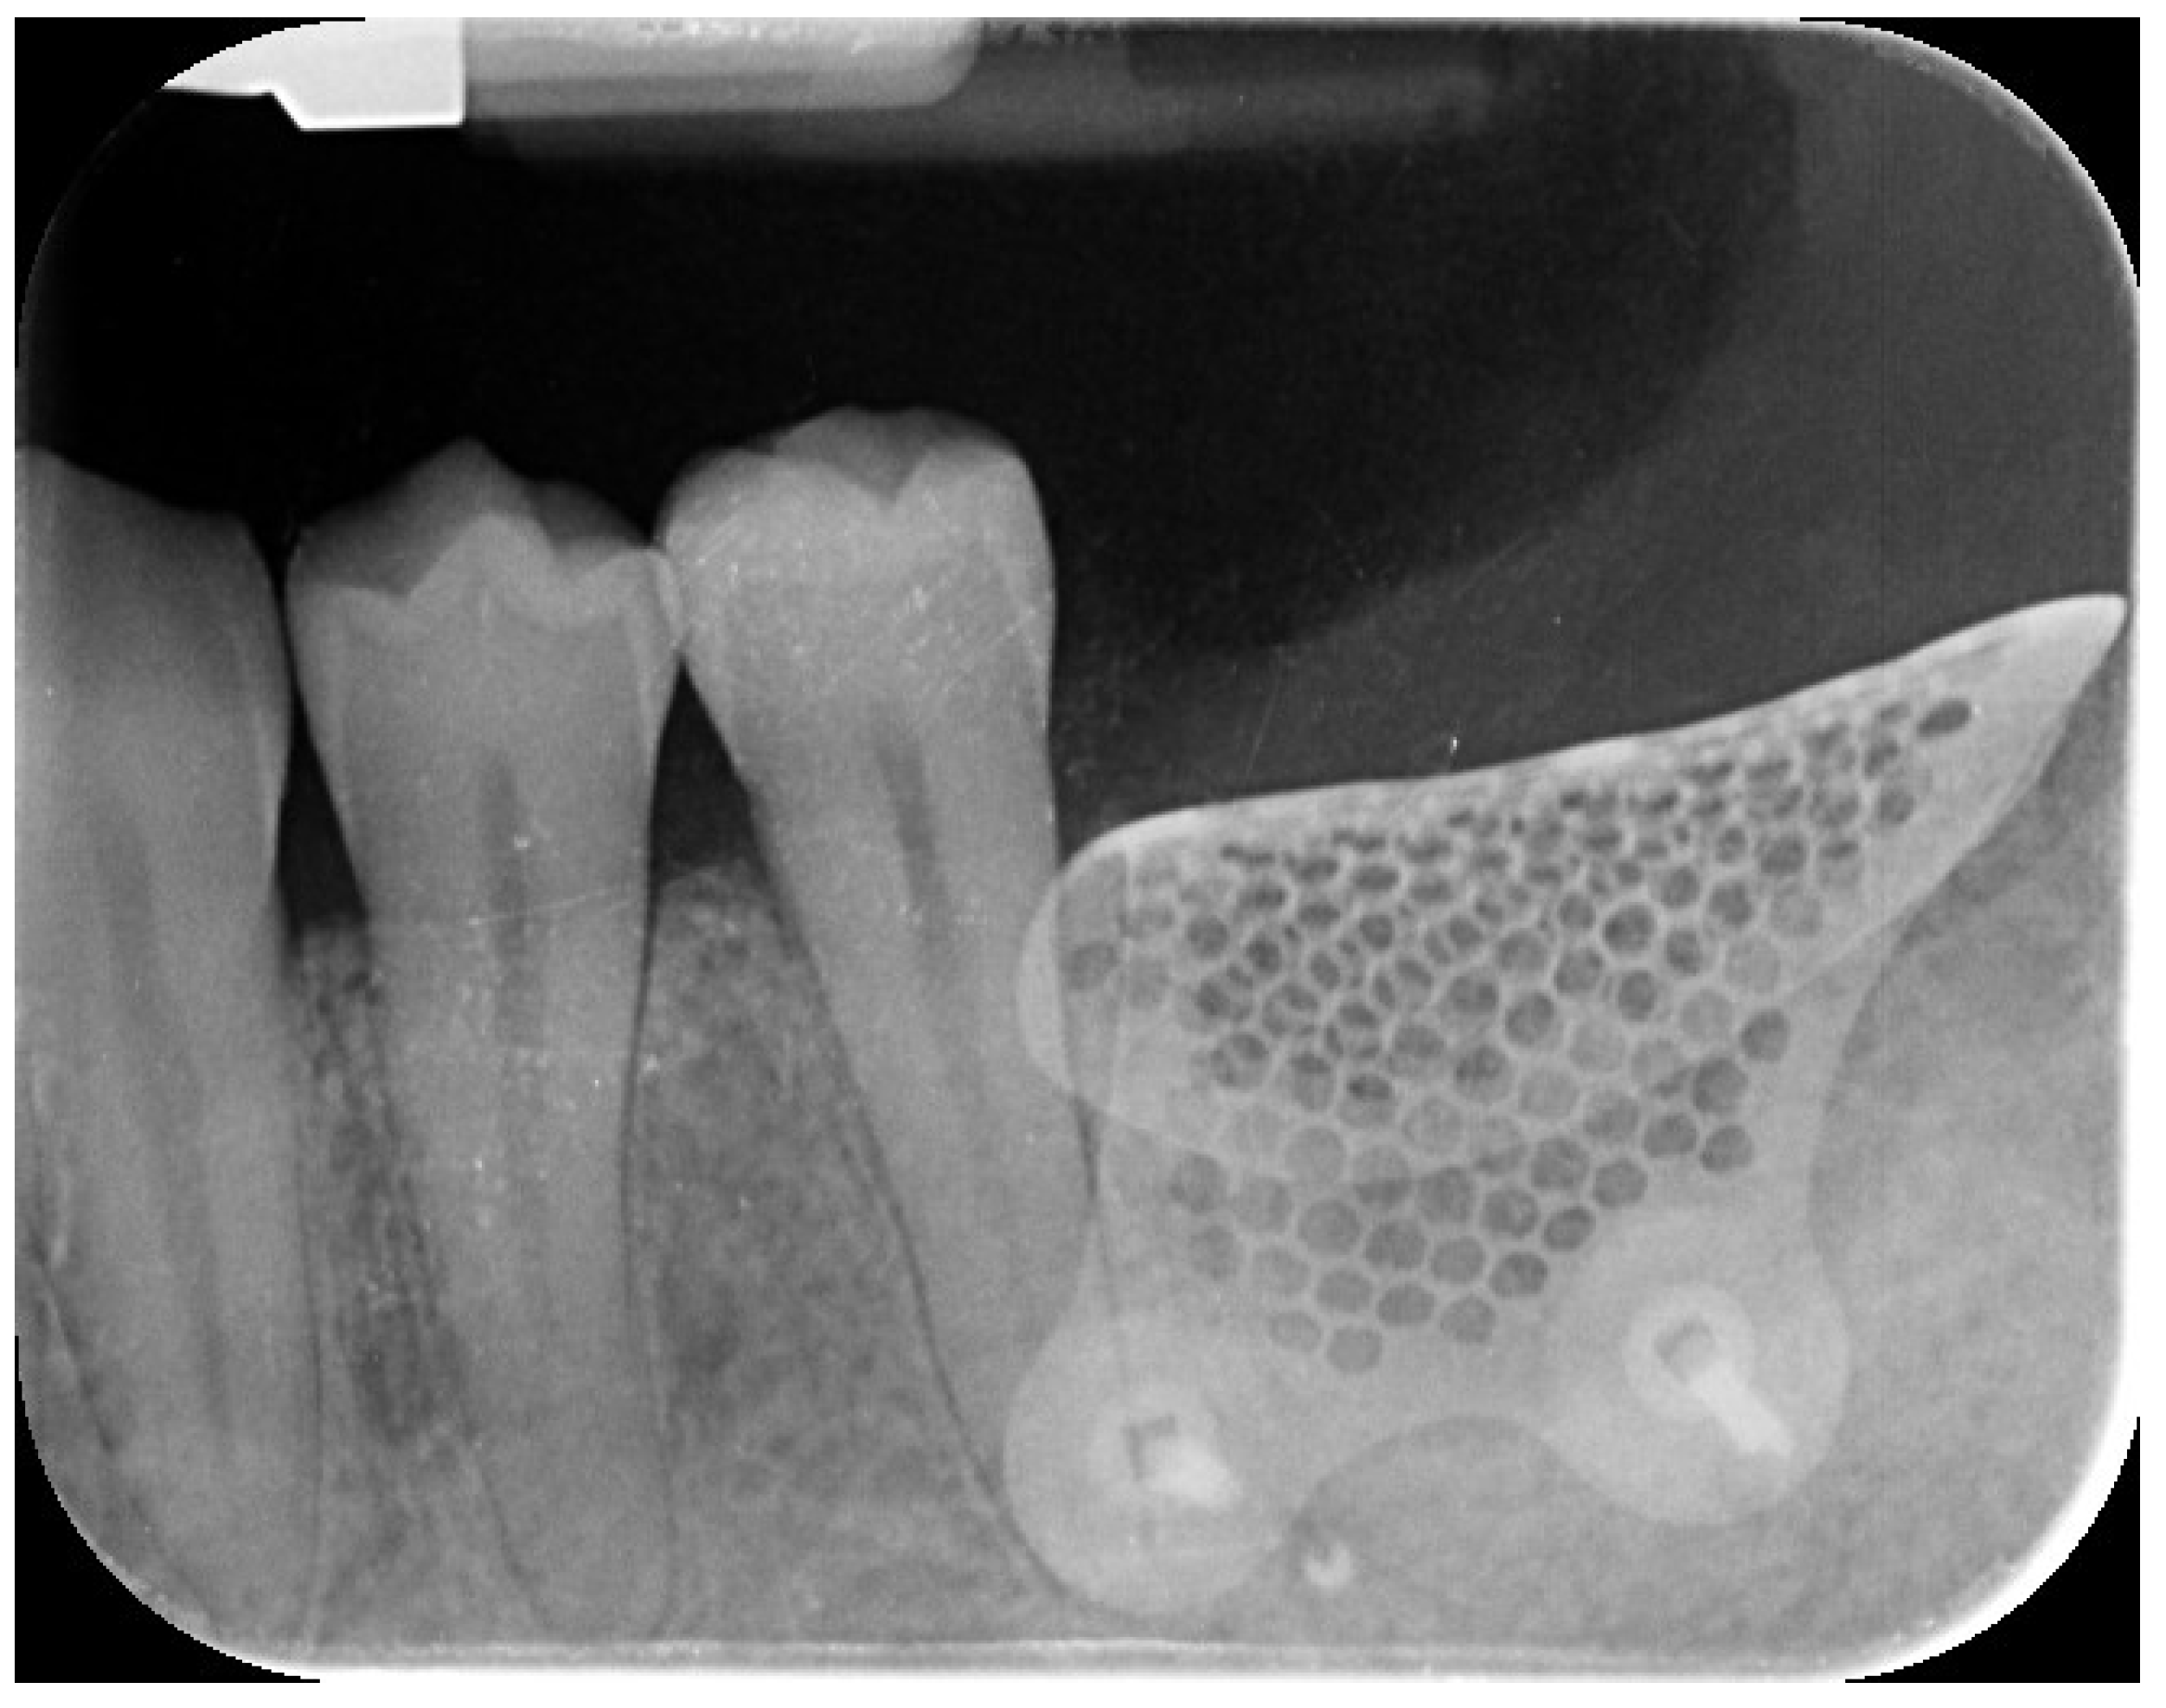

2. Case Summary